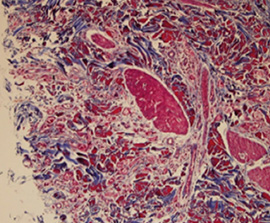

Tissue reaction to pure PDLLA.

Results of histolgical examinationa

쥬베룩 주입 후 6개월 뒤

Masson trichrome 염색